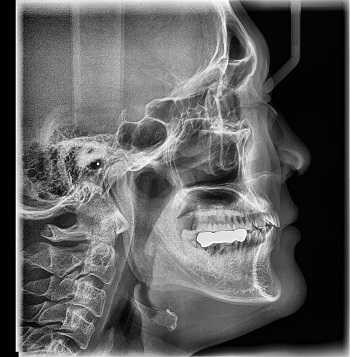

Принцип работы рентгеновского аппарата заключается в том, что рентгеновские лучи, проходя через разноплотную среду исследуемой области, по-разному ослабляются: более плотная костная ткань в значительной степени поглощает рентгеновское излучение, менее плотная подкожно-жировая клетчатка ослабляет его в небольшой степени, а воздух, содержащийся в околоносовых пазухах или легких, не задерживает совсем. Эти неравномерно ослабленные пучки рентгеновских лучей, попадая на светочувствительный слой пленки, формируют рентгенограмму — изображение, которое отображает все структуры исследуемой области, наслаивая их друг на друга. При этом получаемый снимок позволяет определить форму, размеры и строение исследуемой области, выявить или заподозрить структурные нарушения, а исследование в двух или нескольких проекциях позволяет определить локализацию выявленных изменений. Чаще всего рентгенография используется для исследования костей, легких, почек, кишечника.

C самого начала существования этот метод диагностики вызывал у пациентов множество вопросов по поводу воздействия рентгеновского излучения на организм. На сегодняшний день специалисты подтвердили вред рентгена и его способность влиять на развитие нежелательных процессов в организме. Тем не менее, этот метод лучевой диагностики продолжает пользоваться спросом, поскольку требует минимальных затрат.